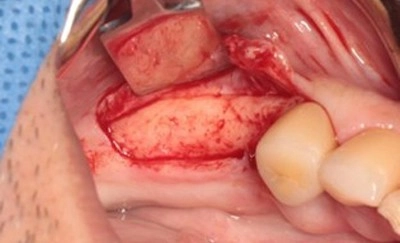

1. 地基重建:精準補骨手術

- 手術目的: 透過專業的骨粉或骨塊移植,將萎縮的齒槽骨(牙床骨)恢復至適合植牙的狀態。

- 關鍵成果: 如圖所示,經補骨手術後,缺牙區的齒槽骨寬度與深度已達到標準,為後續的人工牙根植入提供了理想的生物學環境。

- 專業等待: 補骨手術後需要給予身體足夠的四到六個月癒合期,讓骨粉材料與自體骨組織完全整合,形成強韌穩定的「新地基」。